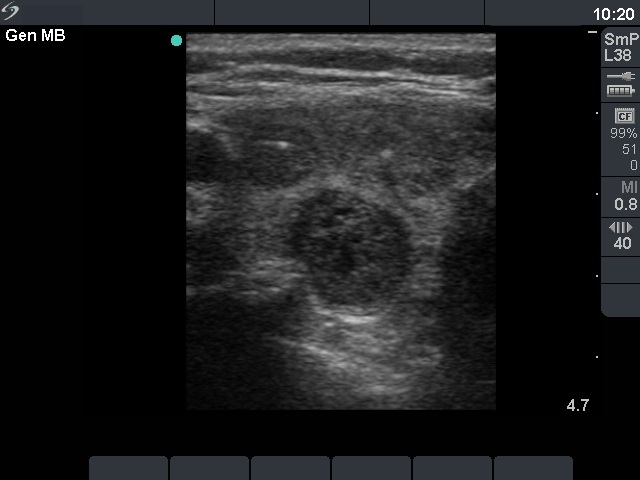

First examination (1st and 2nd rows of images)

Clinical presentation: a 47-year-old woman was referred for evaluation of a multinodular goiter detected on screening. She had no complaints.

Palpation: the right lobe was nodular.

Functional state: euthyroidism with subnormal TSH (TSH 0.18 mIU/L, FT4 18.3 pM/L).

Ultrasonography: the right thyroid contained three nodules, the two ventral lesions were minimally-moderately hypoechogenic, while the dorsal one was hypoechogenic. The latter presented a combined type 2 and type 3 vascular pattern.

Cytology was performed from the dorsal, hypoechogenic nodule and resulted in benign, follicular proliferation. The risk of a carcinoma was estimated to be less than 1%.